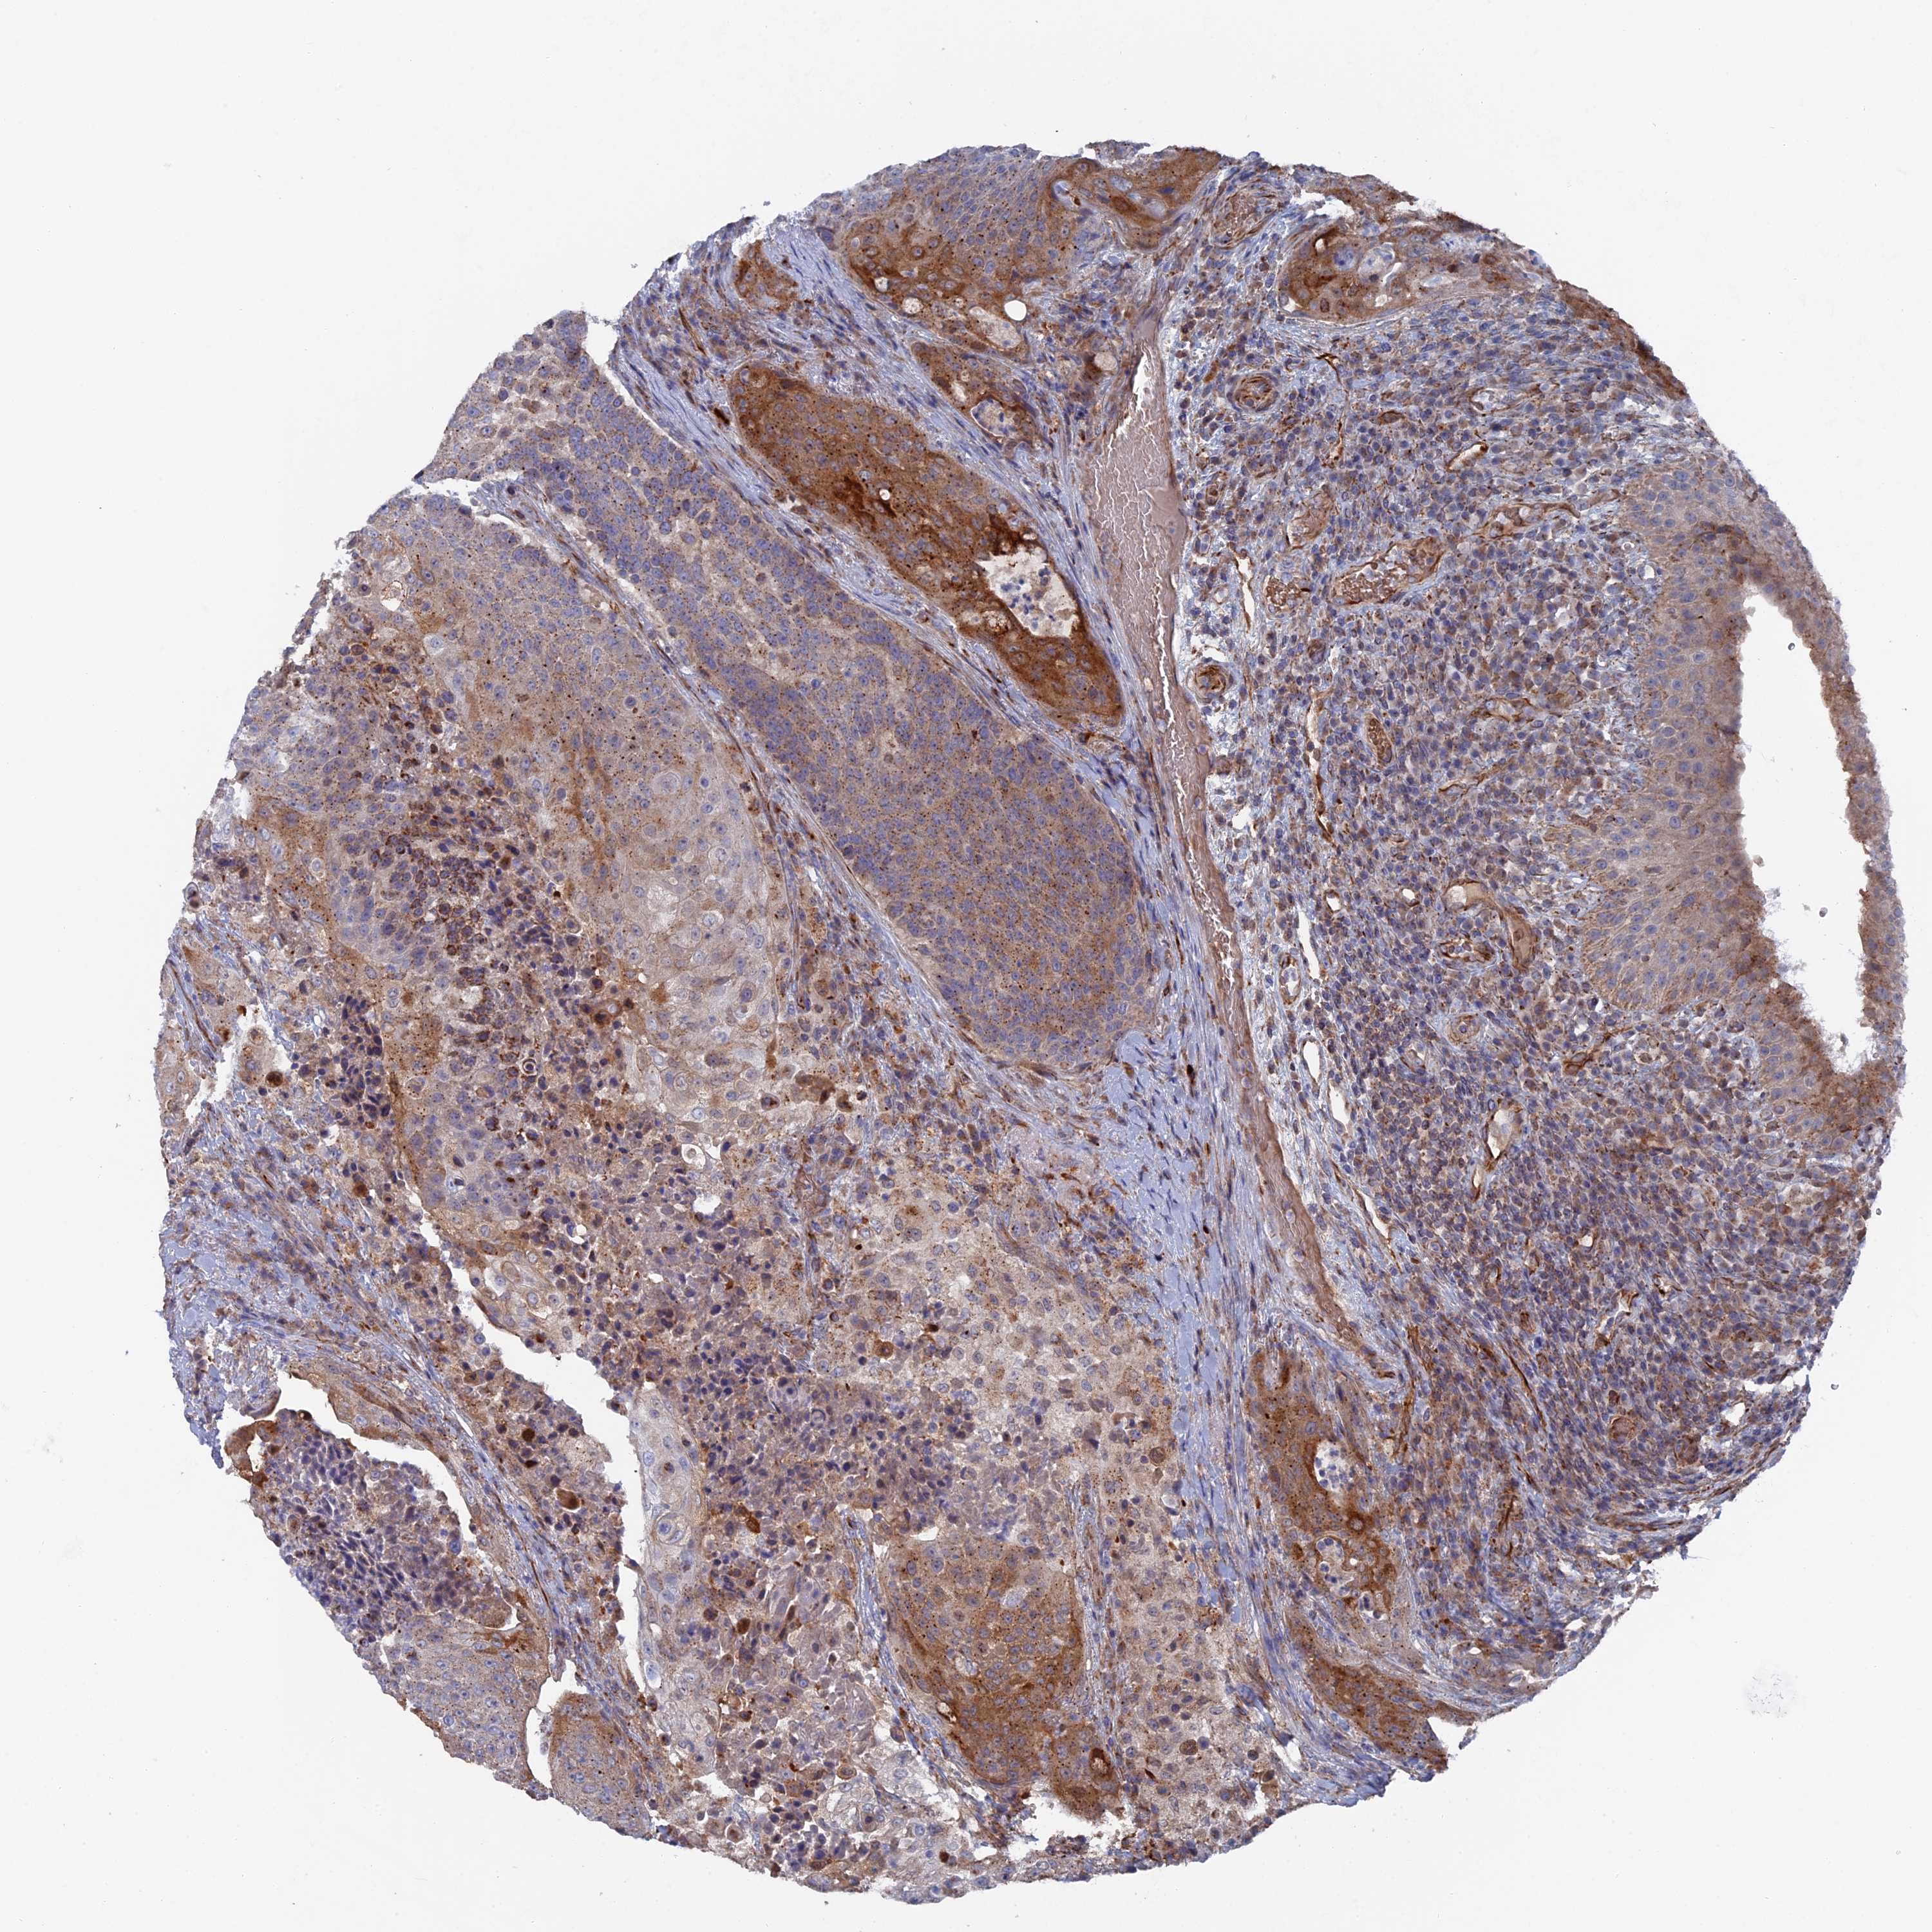

UROTHELIAL CANCER - Protein expressioni

A mouse-over function shows sample information and annotation data. Click on an image to view it in a full screen mode. Samples can be filtered based on level of antibody staining by selecting one or several of the following categories: high, medium, low and not detected. The assay and annotation is described here.

Antibody stainingi

Antibody staining in the annotated cell types in the current human tissue is reported as not detected, low, medium, or high, based on conventional immunohistochemistry profiling in selected tissues. This score is based on the combination of the staining intensity and fraction of stained cells.

Each image is clickable and will lead to virtual microscopy that enables deeper exploration of all samples and also displays staining intensity scores, fraction scores and subcellular localization as well as patient and tissue information for each sample.

Antibody HPA041763

Antibody HPA042096

Staining

High

Medium

Low

Not detected

Intensity

Strong

Moderate

Weak

Negative

Quantity

>75%

75%-25%

<25%

None

Location

Nuclear

Cytoplasmic/membranous

Cytoplasmic/membranous,nuclear

Urothelial carcinoma, Low grade

Urothelial carcinoma, High grade